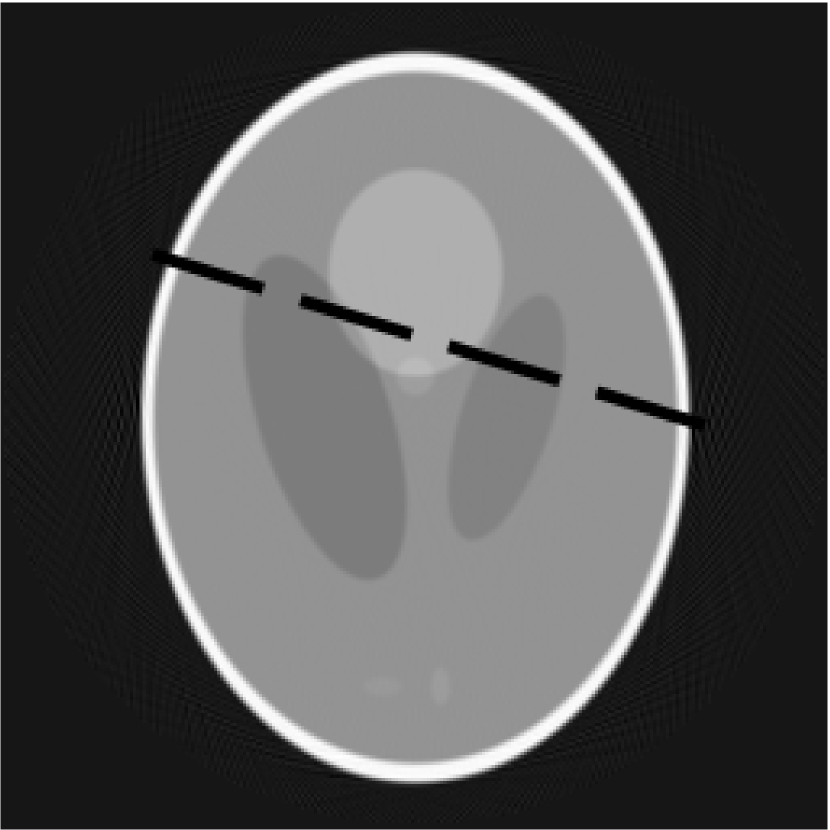

The simplest idea is to divide pixel-wise image, produced by the decomposition algorithm, by image obtained from the FDK. This gives a relative difference between images. An example of using this method is shown in figures 4a, 4b and 4c. FigureΒ 4a is a slice reconstructed by the FDK, figureΒ 4b - by the FDK-OD and figureΒ 4c shows a result of pixel-wise division of these 2 slices.

Tests with Shepp-Logan phantom show that decomposition almost doesnβt affect uniform regions of slice, thus blurs edges and the borders. Skip of 1 decimation stage significantly decreases the blur and helps to preserve sharp borders. This can be seen on the profile comparison (figureΒ 6) for the objects reconstructed with FDK and with our algorithm (5 stages of decomposition, 1 decimation stage is skipped). Corresponding slices are shown in the figures 5a and 5b.